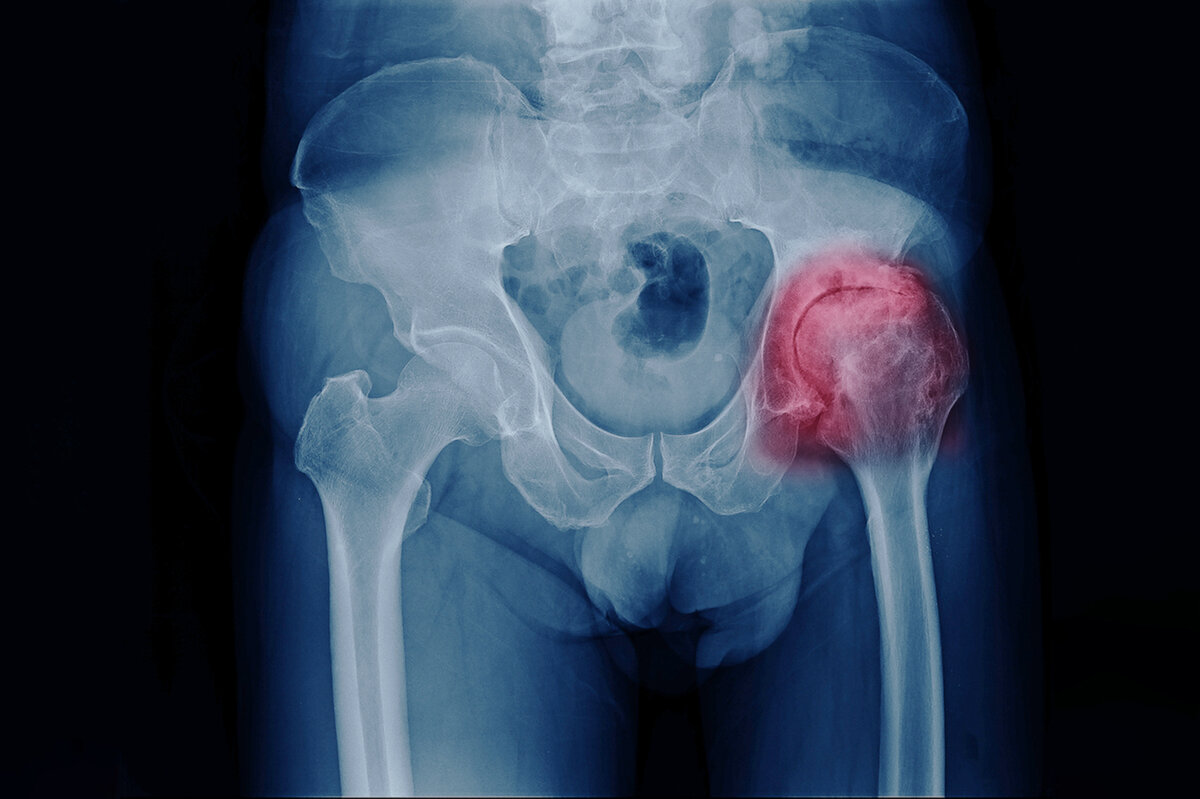

Коксартроз: характер заболевания, причины, симптомы, лечение без операции

Коксартроз — это часто встречающаяся разновидность артроза, развивающаяся в 80% случаев с возрастом. Требует своевременной и квалифицированной помощи. Без медицинского вмешательства заболевание может прогрессировать, приводить к проблемам с активностью, с самостоятельным передвижением.

Изображение взято из свободного источника

Это дегенеративная патология, которая поражает тазобедренный сустав (один или два). Представляет собой дистрофию тканей, развивающуюся сильнее по мере нарастания возрастных изменений. Среди причин заболевания чаще всего называют такие факторы: